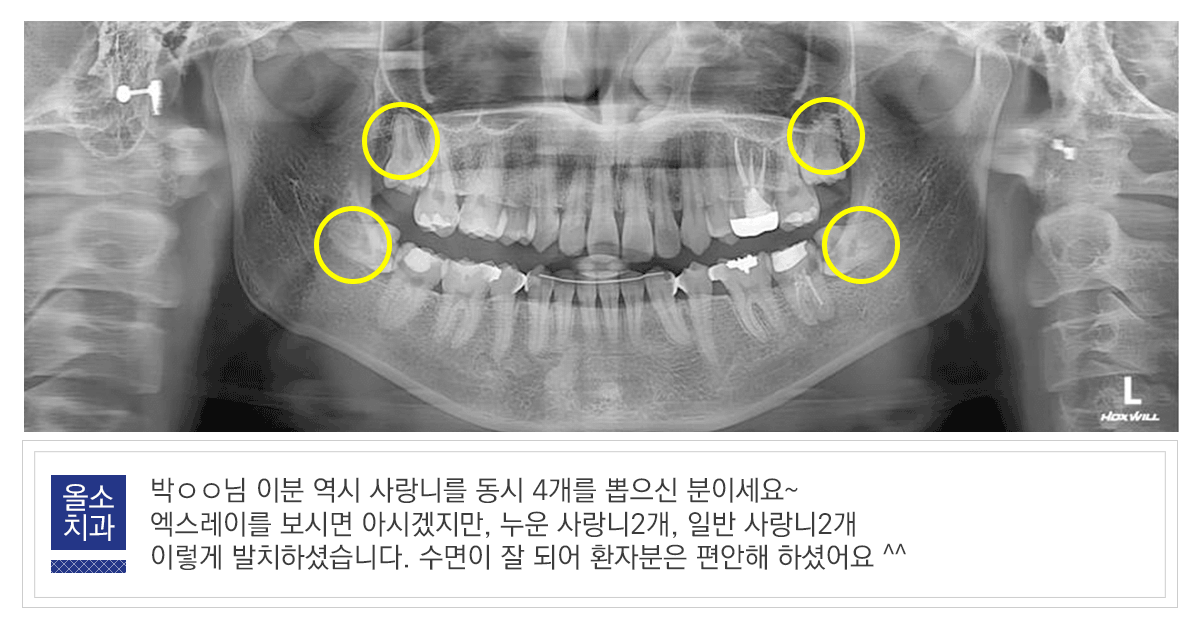

환자 분의 상황에 맞는 발치 계획이 필요하기 때문에 사랑니 발치 시기는 치과에 내원하시어 방사선 사진 및 CT 촬영 등을 통해서 사랑니의 위치를 정확히 파악한 다음, 의료진과 상의하는 것이 핵심입니다.